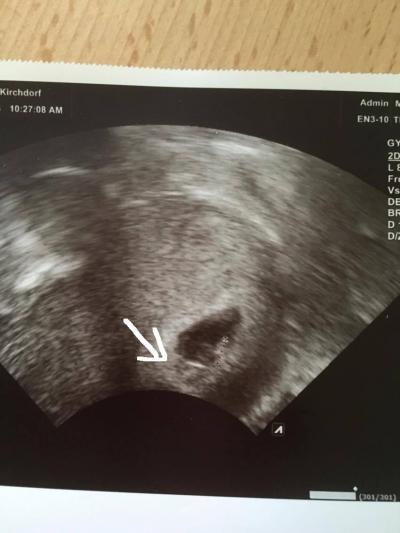

Hey Mädels. Ich finde, auf dem Bild siehts so aus, als ob da ein zweites Baby wäre. Das war 7 ssw. Habe erst am 7 November den nächsten Termin. Wenn das kein zweites Baby ist, was ist das dann? Ich finde, es sieht aus, als wäre die Fruchtblase geteilt. Warscheinlich spielt mir mein Hirn einen Streich. Was meint ihr?

Bild zu Ist da ein zweites Baby??? - Schwanger - wer noch? Rund um die Schwangerschaft

Dein Hirn spielt dir einen Streich. Das ist wahrscheinlich der Dottersack.

ok. Den Dottersack sieht man aber oberhalb neben dem Baby gut.

Naja er hat eben nicht das beste Gerät und er hat auch lange geschaut. Vielleicht wollte er noch nichts sagen. Ich hab schon oft gehört, dass sich der Zwilling dann erst etwas später zeigt. Also bin ich doch noch nicht ganz bekloppt, wenn du da auch was siehst. Ich finde eben, dass es aussieht, als wäre die Fruchtblase geteilt und in dem kleinen Eck unten wäre was drin. Ich finds halt komisch. Wenn man im Internet so Ultraschallbilder von Zwillingen anschaut, sind die auch mit so einem stark weißem Strich getrennt, wenn die Fruchtblasen eng beisammen sind.

Das sind definitiv keine zwillinge. Meine hat man in der 8 ssw klar gesehen. Es kommt noch ab und zu vor das ein Zwilling übersehen wird aber wenn sogar du als Laie meinst ihn zu sehen dann hätte der Fa ihn erst recht erkannt